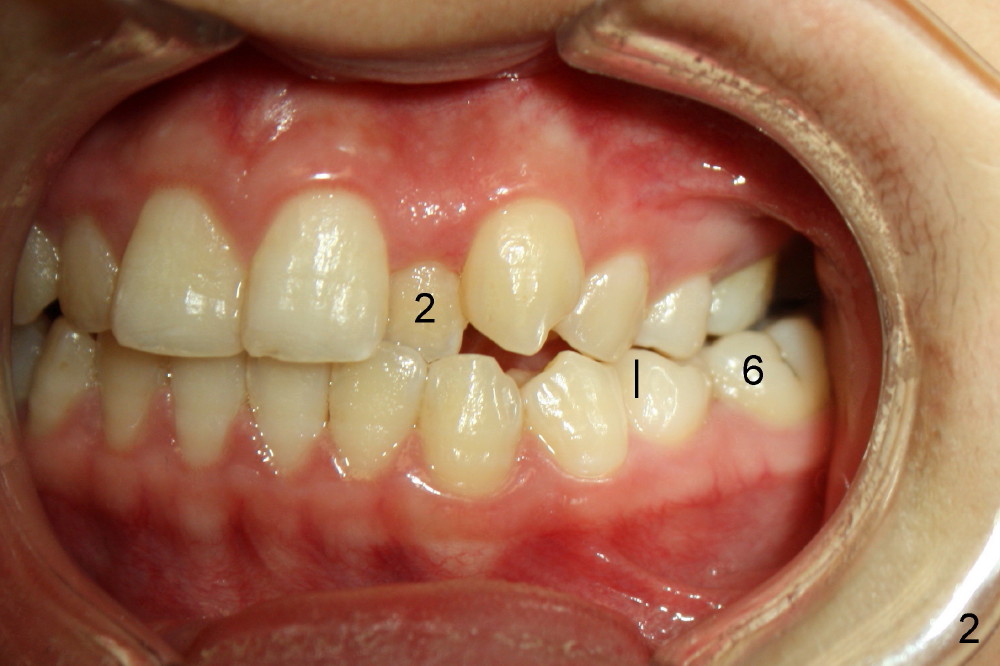

Ms. Xu, 16 years old, has bilateral posterior and UL 2 cross bite (Fig.1,2). L5s rotate (Fig.1-3: black lines).

Another one month later, UL2 is moved labially and a bracket is placed (upside down in order to fix torque problem associated with cross bite correction). Surprisingly, it works perfectly: UL2 orientation is right (Fig.12,13,14). The distal diastema (Fig.14 <) is to be closed by power chain. The palatal expander is removed since the posterior cross bite has been a little overcorrected (Fig.14,15, as compared to Fig.1,2,4-7).